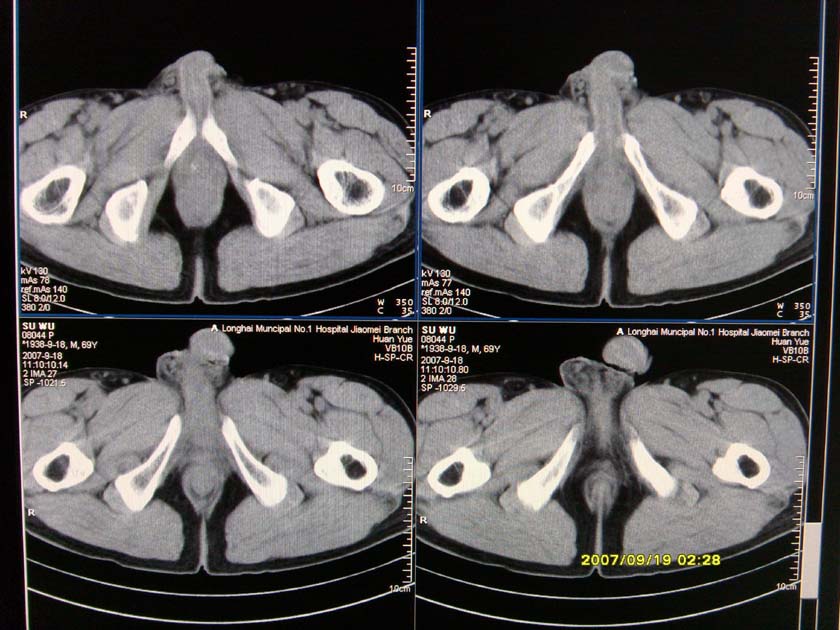

以下是引用xclzq_910在2007-9-19 16:58:00的发言:[br]直肠壁增厚,管腔偏移,直肠癌可能性大

以下是引用宝天曼在2007-9-19 21:11:00的发言:[br]根据直肠壁不规则增厚,考虑直肠肿瘤,不过最后的确诊还是需要肠镜.